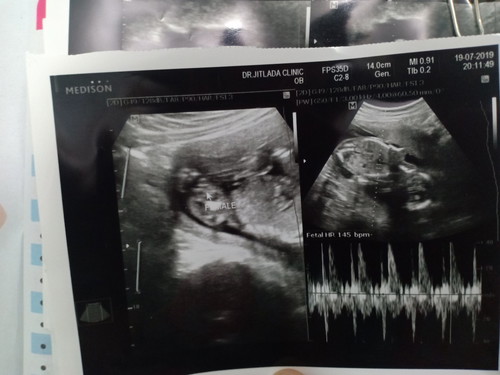

ดูไม่ออกค่ะ แต่ในใบซาวเค้าบอก หญิงค่ะ

Female =เพศหญิงค้ะแม่